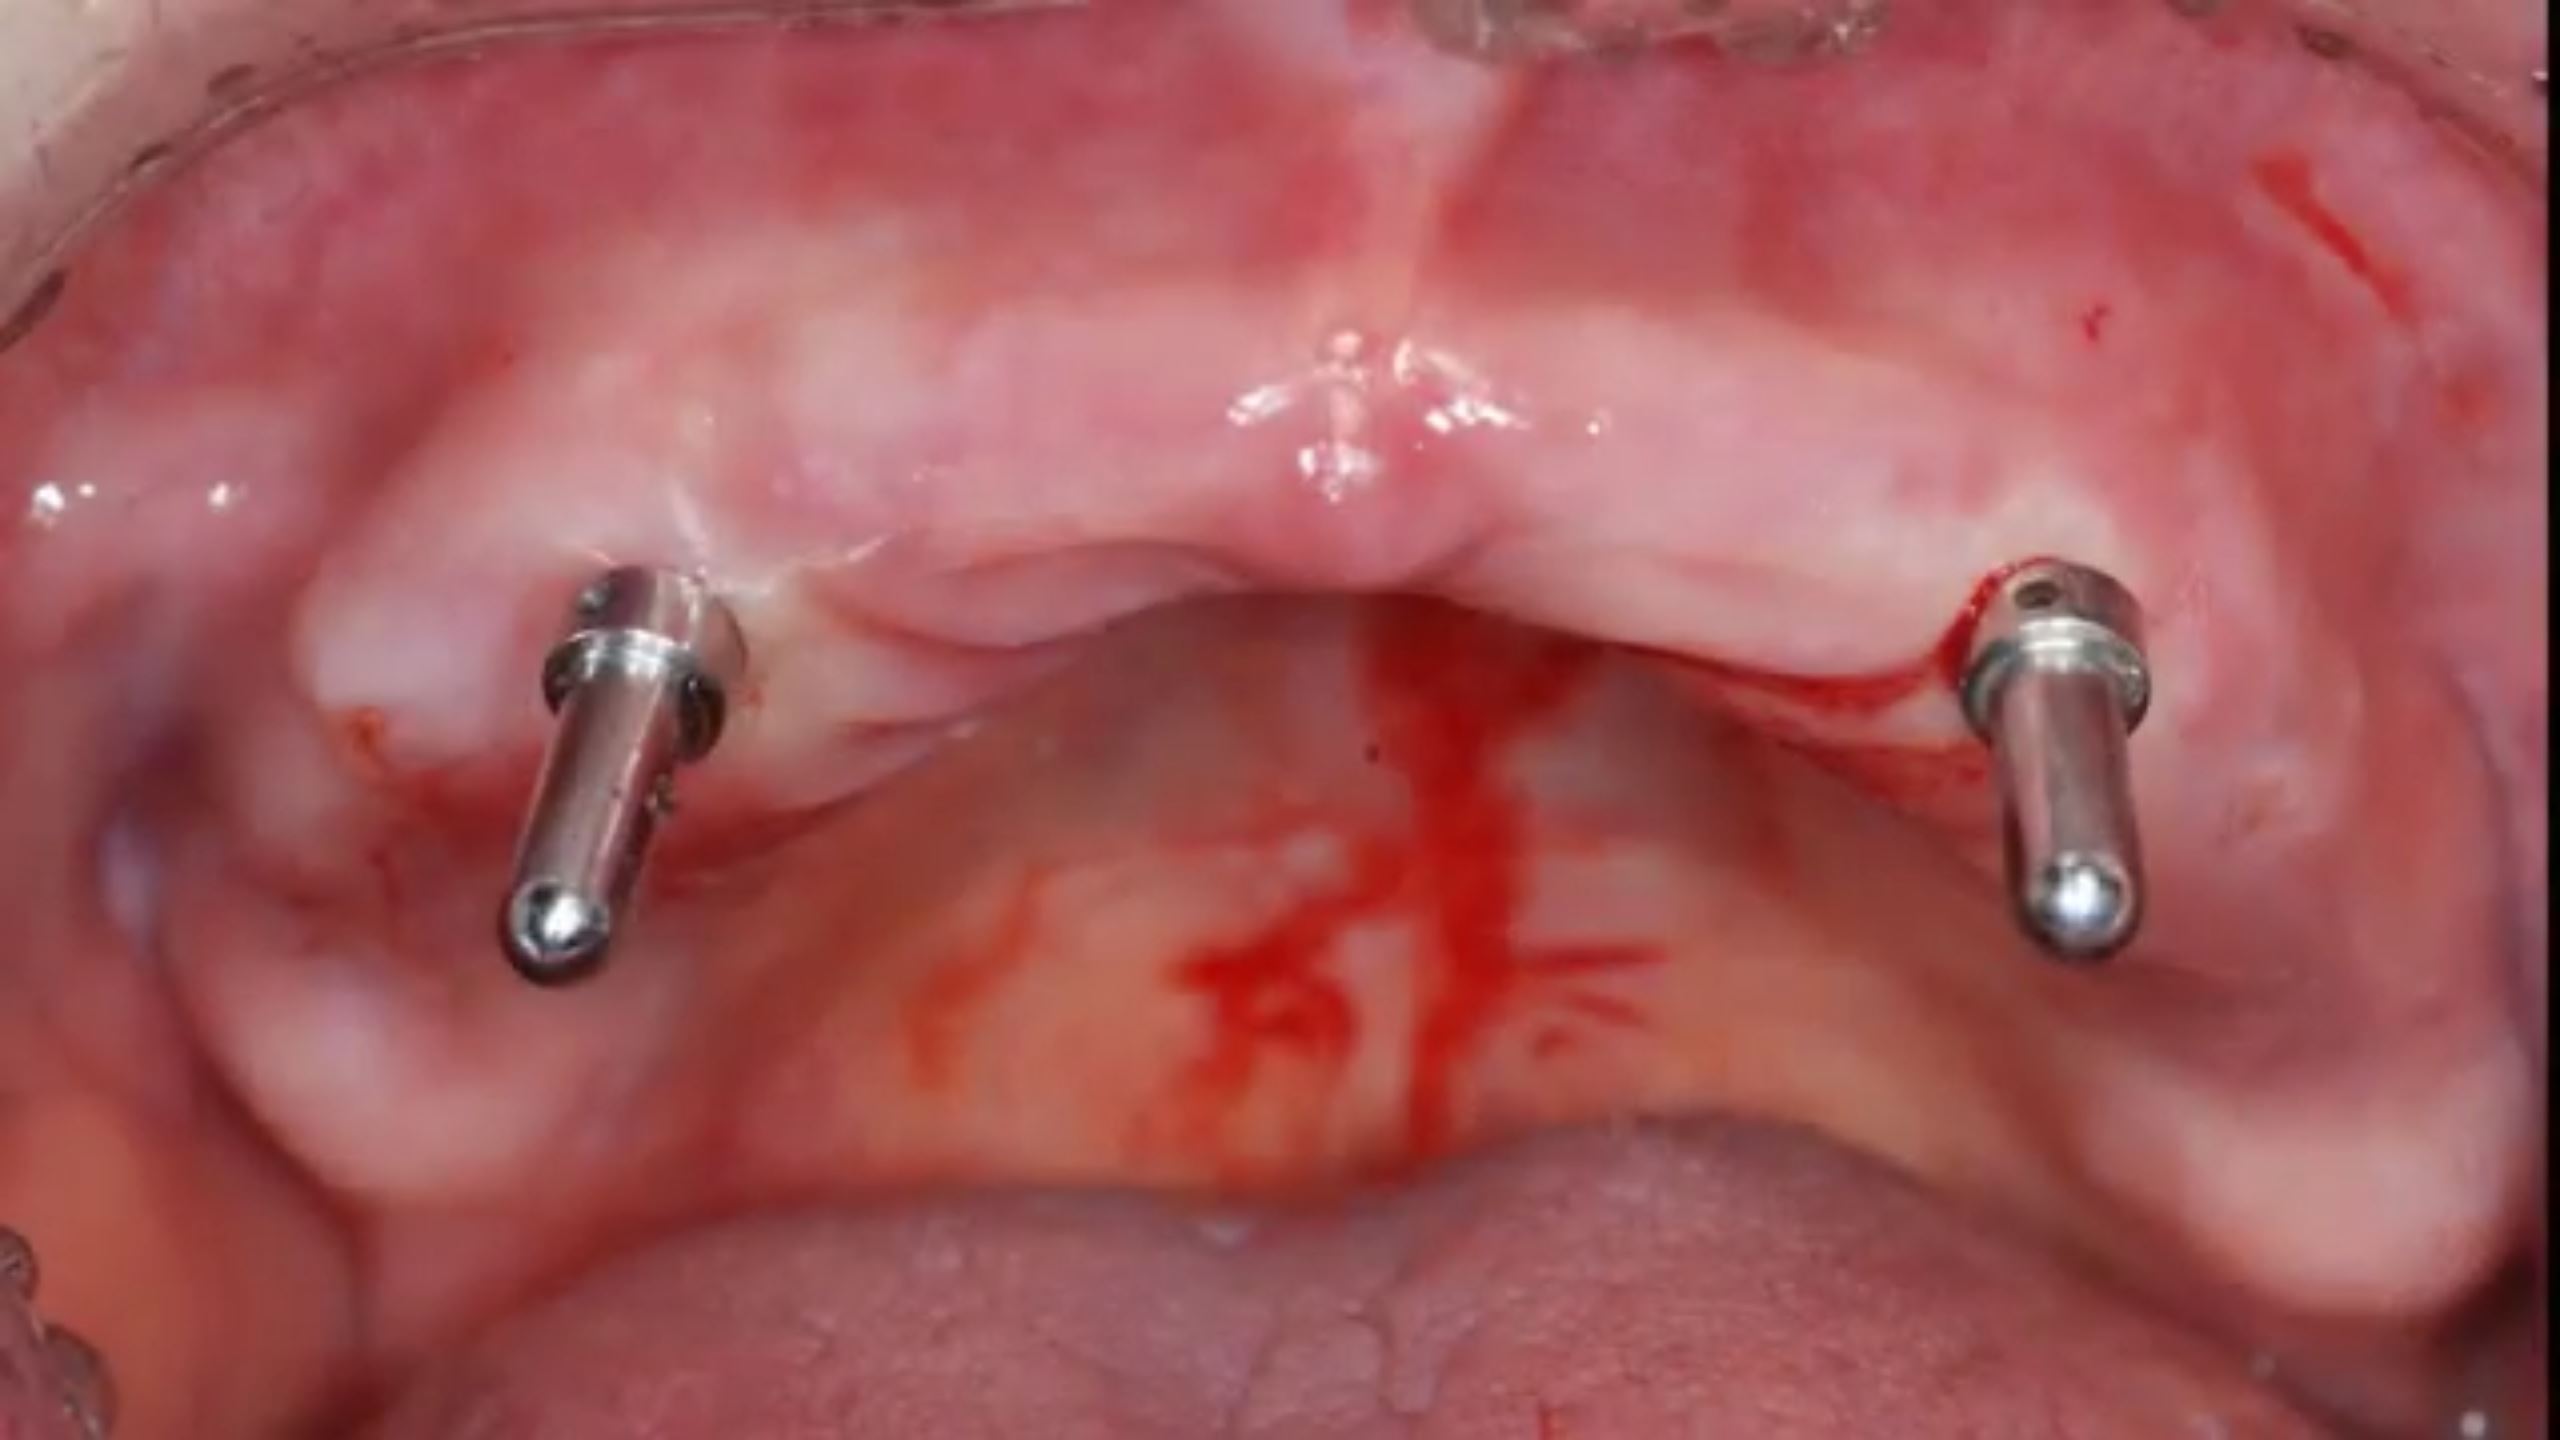

All on six R2GATE Guide Surgery

#11,#13,#16,#21,#23,#26,Digital full mouth prosthetics,Digital Guided Surgery,Edentulous,Flapless,MEG Engine,MEG-TORQ,MEGA ISQ,R2GATE Guide,R2GATE Surgical Kit(AnyRidge),video